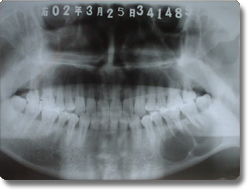

下颌骨肿瘤的手术治疗以往均采用口外颌下区皮肤切口,面部遗留疤痕。我科学习国外的先进方法,运用先进的手术器械,采用经口腔内切口入路方法,对下颌骨良性肿瘤,先行肿瘤切除,再同时采用钛合金成型再造板行下颌骨肿瘤切除后骨缺损缺损的一期修复。该方法的优点是下颌骨肿瘤的切除和骨组织修复再造均经口腔内切口一次手术完成,不再作面部皮肤切口,满足了患者的美容需要。该治疗方法与国际最先进水平保持同步。 |